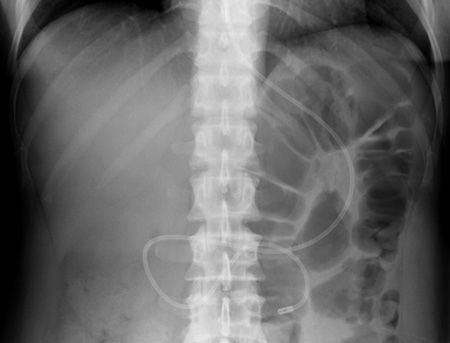

X-RAY QUIZ: Which finding is present on this image?

B: Sail sign

C: Meniscus sign

Start Quiz bit.ly/36i1txn